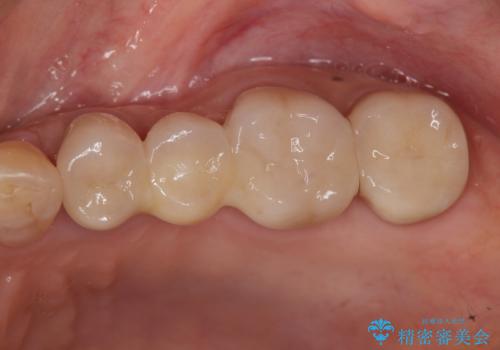

- 「老朽化し古くなった銀歯を白いものにやりかえたい。」と希望され来院されました。

銀歯の下には再発した虫歯やセメントの漏出が見られ、丁寧に除去したのちセラミックによるクラウン・ブリッジ補綴を行います。

- 66万円 仮歯 ジルコニアクラウン×6費用は治療当時の料金となります